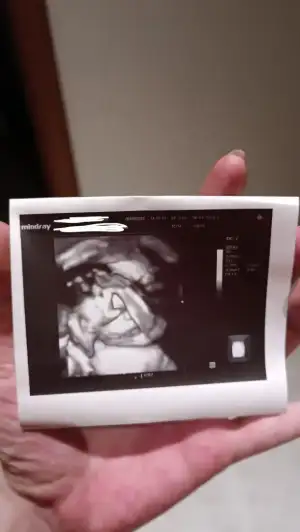

Günaydın kızlar ❤️ dün kontrolümüz vardı 1500gr ve 40 cm olmuş gelişim konusunda doktor bir önceki gittiğimizde 5 gün gerilik var dikkat et fln demisti ben 2 haftadır çok kafayı takmıştım bugün de 1 hafta küçük ama hiç önemli değil gelişimi gayet güzel şu an tekrar ölçsem belki daha farklı çıkacak takma kafaya dedi. Kendimi tutamadım e hocam siz bana 2 hafta önce böyle böyle demiştiniz ben o kadar çok üzüldüm kafaya taktım ki şimdi böyle diyorsunuz dedim yani adamı sedyeden kalkıp bogazlayasım geldi madem bu kadar takılacak birşey neden beni azarladin valla bu doktorun bipolar olduğuna kanaat getirdim bir günü bir gününü tutmuyor 😂 neyse yine ama yine canım oğlum bize yüzünü göstermedi elleriyle yüzünü kapattı ama o kapatma hareketine bile eriyorum şuna bakın 🫠 servikal uzunluğa niyeyse bu sefer bakmadı gerek görmedi ben de tamam dedim işime geldi. İkidir gözüme birşeyler oluyor bir anda ışık patlıyor sağ gözümle bir yeri göremiyorum onu söyledim ona hemen baktır gözüne pıhtı atıyor ya da göz tansiyonun çıkmış Olabilir dedi bugün gidicem. Size asıl bombayı söylüyorum, benim göbek deliğim çok dışarı çıkmaya ve hafif ağrı yapmaya başlamıştı doktor ultrasona gönderdi babalar gibi göbek fıtığım varmış 😂 çok şükür 9 mm çok büyük değilmiş ama göbekle beraber fıtık da büyürse cerrahi operasyon gerekebilir ama inşallah gerekmez eğer sezaryen olacak olursan ben onu ameliyat sırasında hallederim yama atarım dedi ben de bir ondanım eksikti dedim artık sadece gülüyorum ya 😂 ay cokbuzun oldu hakkınızı helal edin ❤️

Canım valla senin hayırlısıyla zamanında ve artık hiç bir yeni tanı almadan doğurmanı diliyorum artık. 😂Olabilecek her şey sende çıktı. İnşallah bir şey yoktur 🙏 fotoğrafta ellerinin altında dudakları görünüyor 🥹🥹🥹 dolgu dudaklı bir bey gelecek sanırım. O kadar güzeller ki kalbim eriyor fotoğrafların hepsine🌸

Oy evet evet dudaklar ve burun kıvrımı görünüyor doğsa da yesem 🤤 ( aman zamanında doğsun da 😂 ) evet ya bir gebelikte ne olmamalıysa sanırım hepsi teker teker geliyor kombo yaptım hdhdvshsb